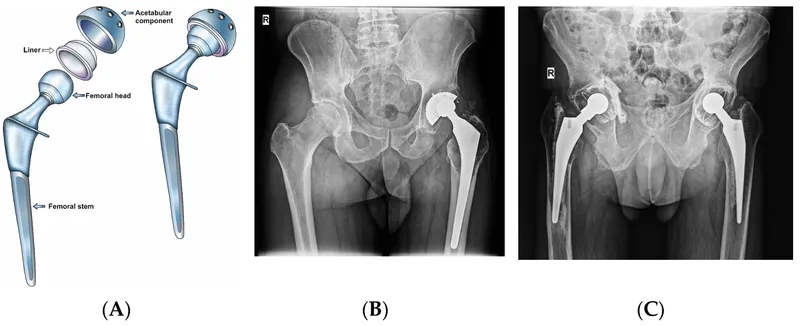

- Fixation: Cemented (PMMA) vs. Cementless (porous coat for ingrowth).

Fixation Methods:

- Cemented (PMMA - Polymethylmethacrylate):

- Mechanism: Mechanical interlock (grout).

- Indications: Typically older patients (e.g., >65-70 yrs), poor bone stock, osteoporosis, irradiated bone.

- Advantage: Immediate stability, allows early weight-bearing.

- Uncemented (Press-fit):

- Mechanism: Initial press-fit stability followed by biological fixation (osseointegration) via bone ingrowth into porous surfaces.

- Indications: Younger, more active patients (e.g., <65 yrs) with good bone stock.

- Advantage: Potential for durable, long-term biological fixation.

- Hybrid: Combination (e.g., cemented femoral stem, uncemented acetabular cup in Total Hip Replacement).

⭐ The "cement mantle" thickness is critical in cemented arthroplasty; ideal is 2-4 mm. An incomplete or uneven mantle can lead to stress concentration and early aseptic loosening.